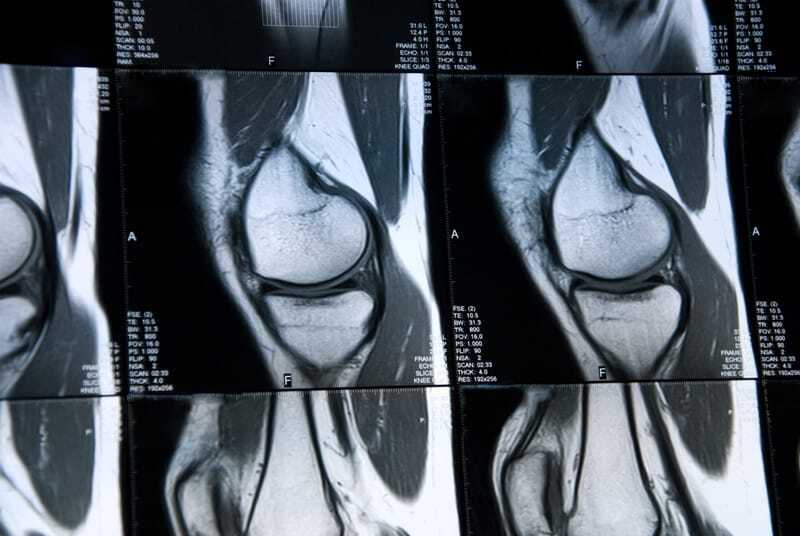

We get many emails from people who had a recent MRI. Some of their MRI reports are deep and comprehensive in their description of an unseeingly insurmountable amount of damage to the person’s knees. The person who sends in the email will sometimes add something in the email to suggest that their MRI is one of the worst that their doctor has ever seen. The funny thing is when we ask, “well how does your knee feel today?” Sometimes we get the answer, “not bad.” How can someone who has one of the worst knee MRIs their doctor has ever seen, have a knee that is “not bad”? That is what a lot of research is focusing on. Below we are going to focus on that research that demonstrates that the MRI may not be telling the truth about their pain source, In fact, new findings say that many MRIs are useless.

I have been providing regenerative medicine injections for more than 25 years. We always treat the patient. We do not treat the MRI. What does this mean? It means that while the MRI is an important tool in seeing what is going on in the knee, it sometimes shows us too much. It sometimes shows us damage that is not bothering or limiting the patient. If you solely relied on what the MRI is showing and never talked to the patient about how their knee felt, there would be a lot more knee surgeries, and a lot more failed knee surgeries and a lot more people who are worse off. There is a lot of research to back this up.

As stated above, I have been providing regenerative medicine injections for more than 20 years. We always treat the patient. We do not treat the MRI. While the MRI is an important tool in seeing what is going on in the knee, it sometimes shows us too much. It sometimes shows us damage that is not bothering or limiting the patient. It may show enough for some to go to a surgery they may not need. If you solely relied on what the MRI is showing and never talked to the patient about how their knee felt, there would be a lot more knee surgeries, and a lot more failed knee surgeries and a lot more people who are worse off.